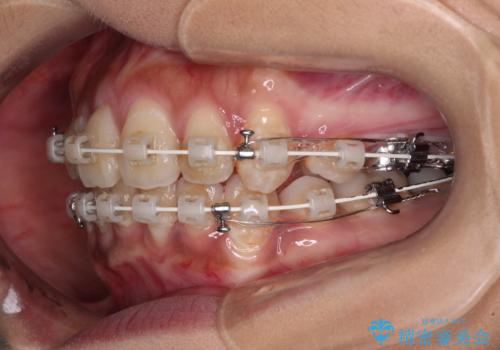

- 矯正装置

- 審美装置

- 2年5ヶ月

- 10-30回